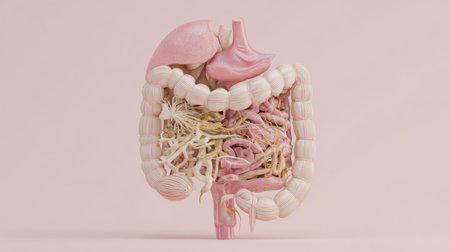

This artistic illustration showcases the human digestive system, highlighting essential internal organs and structures against a soft pink background, ideal for educational content.

This medical illustration showcases a detailed view of the human intestines. It highlights the digestive system with vibrant colors and intricate textures. The composition employs a clear and informative style, possibly for educational or scientific purposes. This image may be suitable for use in medical publications or educational resources.

Human Digestive System Anatomy For Medical Concept 3D Illustration

This colorful representation highlights the intricate structure of the human digestive system, emphasizing the intestines and crucial organs involved in digestion.